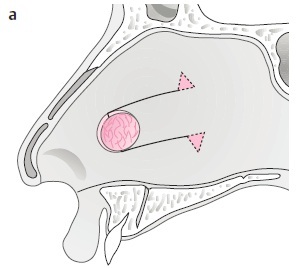

2. 選定模版: 在修補過程中,除了雙側鼻中隔黏膜外,會希望中間放置額外組織支撐並作為黏膜生長的模版。可選材料包含:骨膜(mastoid periosteum)、筋膜(temporalis fascia)、心包膜(pericranium)、鼻中隔軟骨/硬骨、 fascia lata、大腿外側筋膜,以及人工真皮(alloderm)。

→ 以價格考量:自體鼻中隔、耳軟骨或筋膜最適合、便宜又好用,其中以 Temporalis fascia 最常使用。

→ 以手術時間考量:Alloderm 或捐贈 fascia lata 較適合,不需額外取皮,縮短手術時間。

3. 手術方式(小洞): 如破損較小,可使用局部擴張或轉位(local flap),在內視鏡下以鼻中隔黏膜皮瓣或下鼻甲皮瓣修補。

4. 手術方式(大洞): 若破損較大,可考慮開放式鼻整形(Open rhinoplasty)修補,使用鼻道下方黏膜。

此方式為目前成功率最高的修補方式,也是最常使用的手術法。